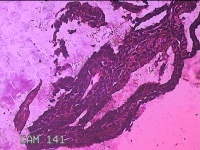

宫腔内容物

性别

女

年龄

临床诊断

一般病史

无

标本名称

大体所见

灰白暗红色不规则碎组织2.8x2x0.7cm一堆。

图1